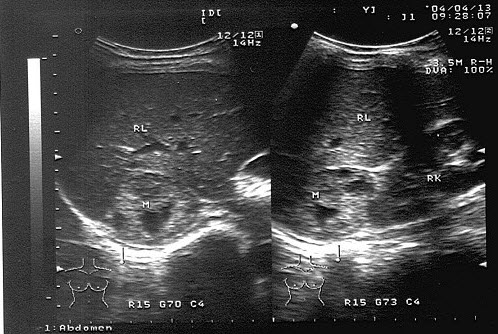

34、单项选择题

男,11岁,右侧阴囊空虚,左侧睾丸可触及,右侧腹股沟区可探及低回声肿块,如图所示,考虑为()

A.隐睾

B.淋巴结

C.腹股沟疝

D.腹股沟肿瘤

E.以上都不是